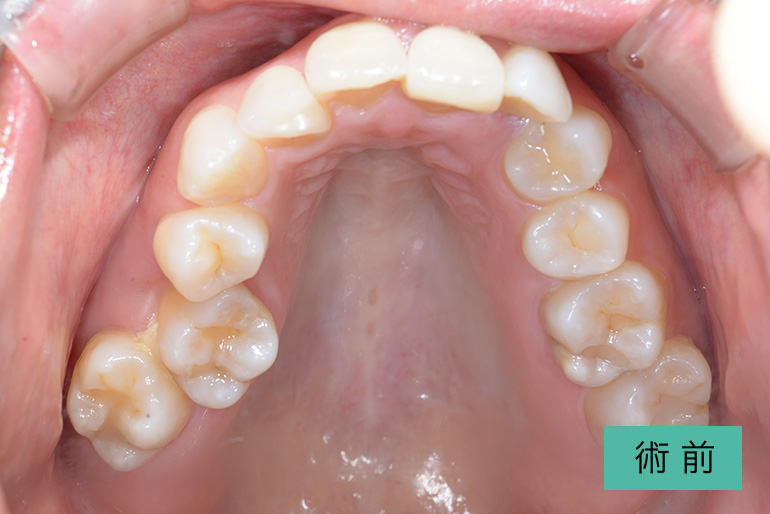

| 治療内容 | 上顎前歯右上3番から左上3番のセラミック冠 |

| 治療期間・回数 | 約1ヶ月、3回 |

| 費用(税込) | ¥990,000(165,000/1本)(補綴費用) ※自由診療 |

| リスク・副作用 | 疼痛、補綴物の脱落、咬合違和感、破折 |